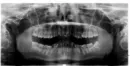

Хотелось бы получить Ваше мнение по данному снимку. В частности 45 зуб нет никаких симптомов, в прошлом тоже не было, также 37 и 38 зуб. 38 зуб собираюсь удалять.

Насколько сложным может быть удаление? Насколько затронут 37 зуб? Есть ли другие видимые особенности, помимо прикуса?

Судя по расположению Ваших зубов на снимке, Вам показано ортодонтическое лечение с применением брекет-системы. Насколько позволяет качество снимка оценить состояние зуба 4.5, никаких изменений в данном зубе нет, помимо неправильного положения.

Скорее всего, Вам придется удалить все восьмые зубы по ортодонтическим показаниям для создания места в зубном ряду.